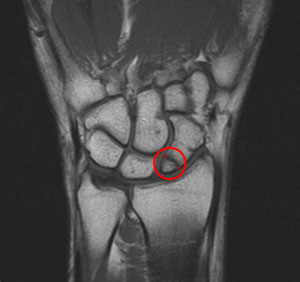

" I am a professional drummer and went to see Paul when I began to develop severe tension, numbness and shooting pains in the muscles along my forearm and in and around my wrist and thumb. Paul realised that my symptoms were probably due to a fractured Scaphoid bone (circled in red) in my wrist which had occured two years previously. I was getting these sensations every time I played and was in a lot of discomfort, practically unable to play. Paul realised that my symptoms were probably due to a fractured Scaphoid bone in my wrist which had occured two years previously.